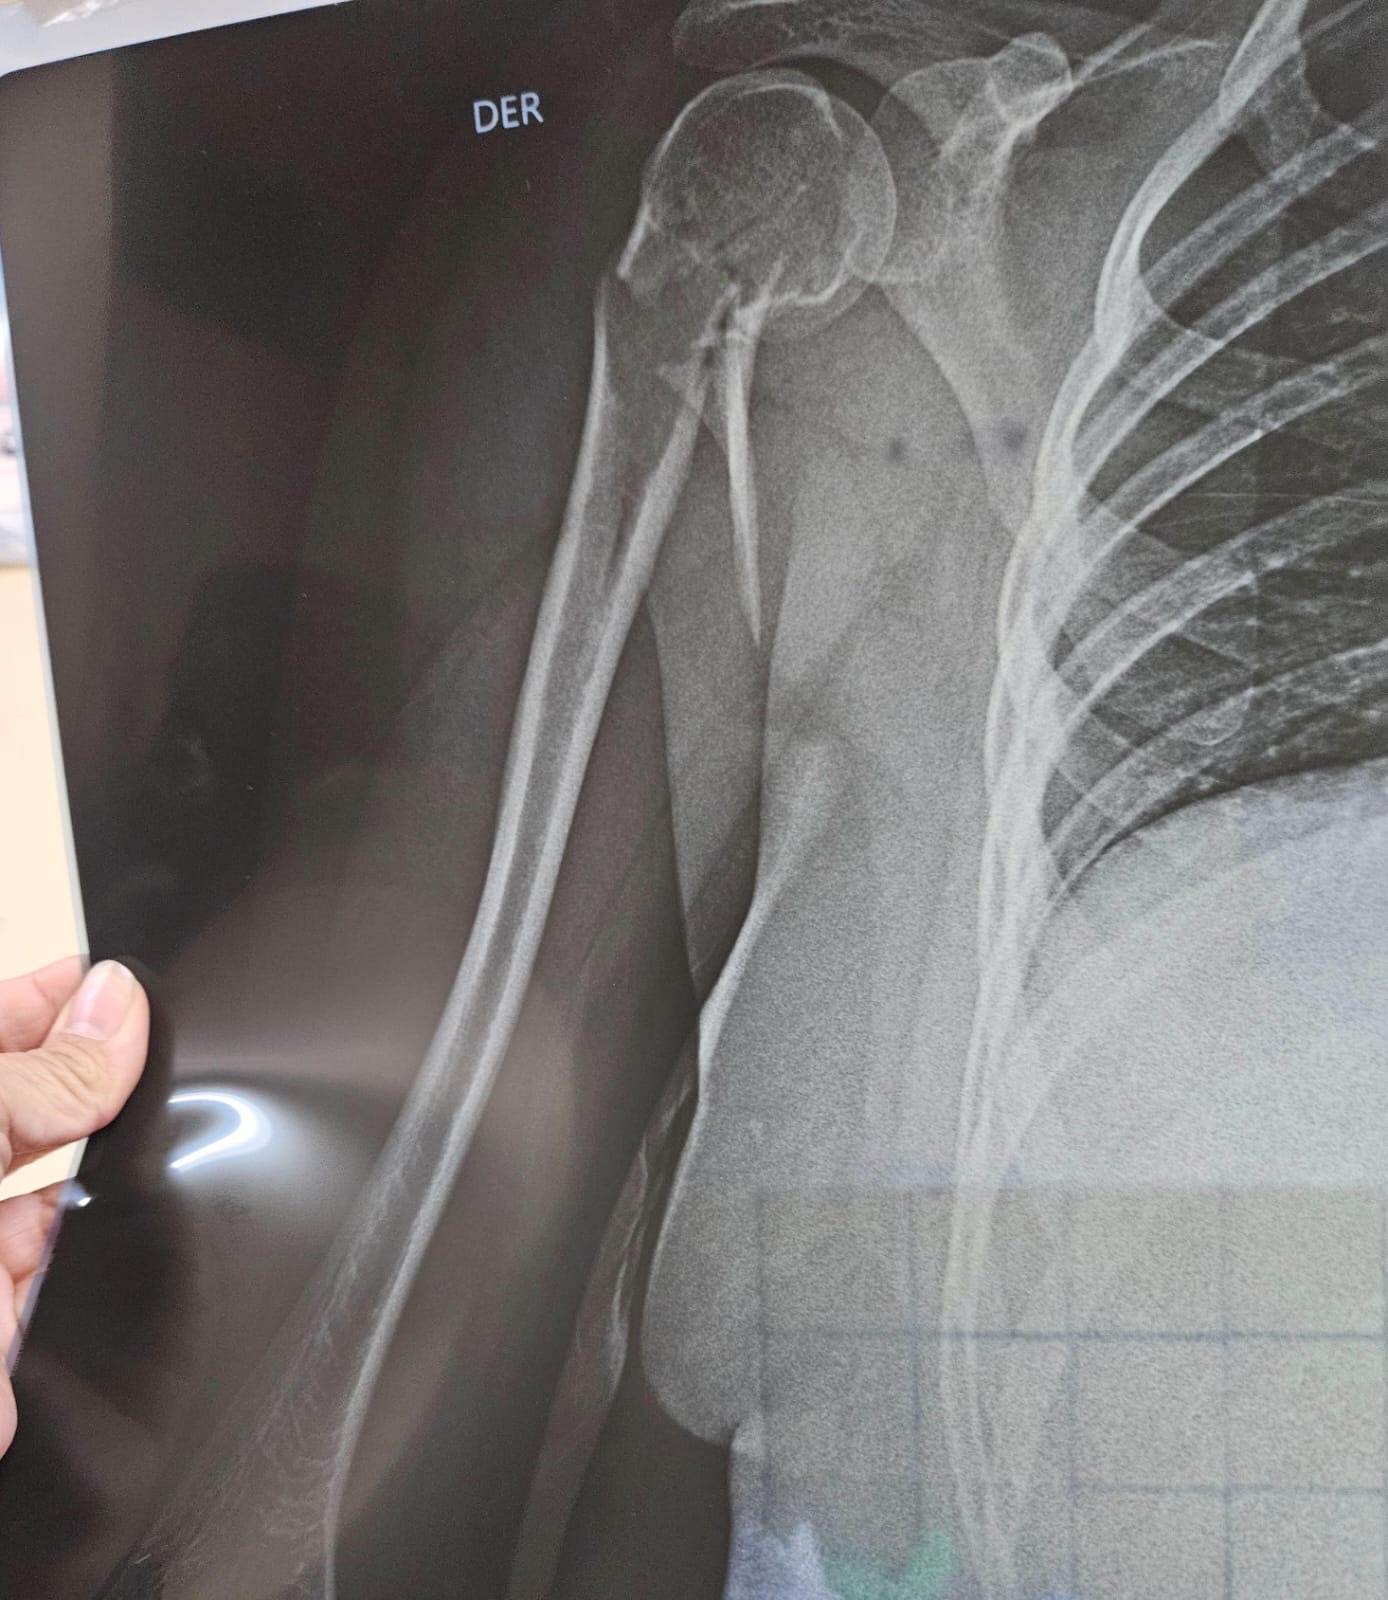

7 months ago I was involved in a serious car accident that resulted in a severe fracture. What followed was a whirlwind of pain and uncertainty. Because of the complexity of the injury, I had to undergo two major surgeries to stabilize my condition and begin the long process of healing.